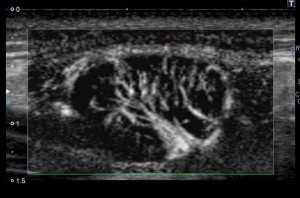

悪性リンパ腫(モノクロ表示モード)